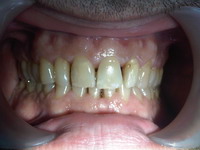

Obturatii nefizionomice pe

dintii frontali

Situatie initiala

Coroane ceramica pe suport zirconiu